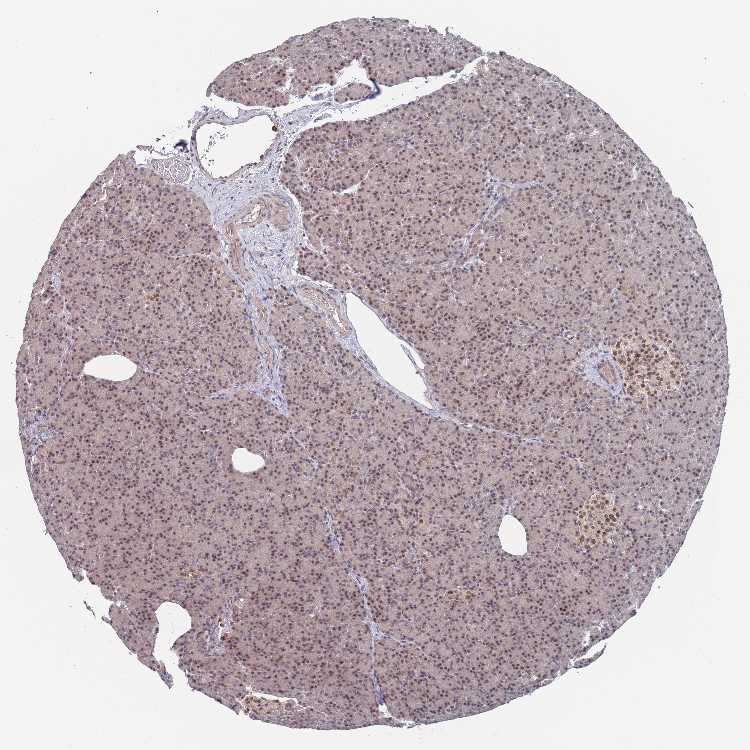

TISSUE PRIMARY DATA PANCREAS Show tissue menu

PANCREAS - Antibody stainingi

Antibody staining in the annotated cell types in the current human tissue is reported as not detected, low, medium, or high, based on conventional immunohistochemistry profiling in selected tissues. This score is based on the combination of the staining intensity and fraction of stained cells.

Each image is clickable and will lead to virtual microscopy that enables deeper exploration of all samples and also displays staining intensity scores, fraction scores and subcellular localization as well as patient and tissue information for each sample.

Antibody HPA046900

Exocrine glandular cells Medium

Pancreatic endocrine cells Medium